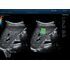

STE (Sound Touch Elastography)

STE интегрирована с эксклюзивной технологией Ultra-Wide Beam Tracking от Mindray для двумерной эластографии сдвиговой волной в реальном времени. Специализированные измерительные инструменты позволяют проводить количественный анализ модуля упругости с высокой точностью.